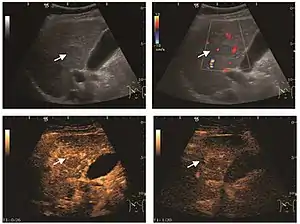

It is the most common liver tumor with a prevalence of 0.4 – 7.4%. It is generally asymptomatic but also can be associated with pain complaints or cytopenia and/or anemia when it is very bulky. It is unique or paucilocular. It can be associated with other types of benign liver tumors. Characteristic 2D ultrasound appearance is that of a very well defined lesion, with sizes of 2–3 cm or less, showing increased echogenity and, when located in contact with the diaphragm, a "mirror image" phenomenon can be seen. When palpating the liver with the transducer the hemangioma is compressible sending reverberations backwards. Doppler exploration reveals no circulatory signal due to very slow flow speed. CEUS investigation has real diagnosis value due to the typical behavior of progressive CA enhancement of the tumor from the periphery towards the center. The enhancement is slow, during several minutes, depending on the size of hemangioma and on the presence (or absence) of internal thrombosis. During late (sinusoidal) phase, if totally "filled" with CA, hemangioma appears isoechoic to the liver. Deviations from the above described behavior can occur in arterialized hemangiomas or those containing arterio-venous shunts. In these cases, differentiation from a malignant tumor is difficult and requires other imaging procedures, follow up and measurements of the tumor at short time intervals.[4]